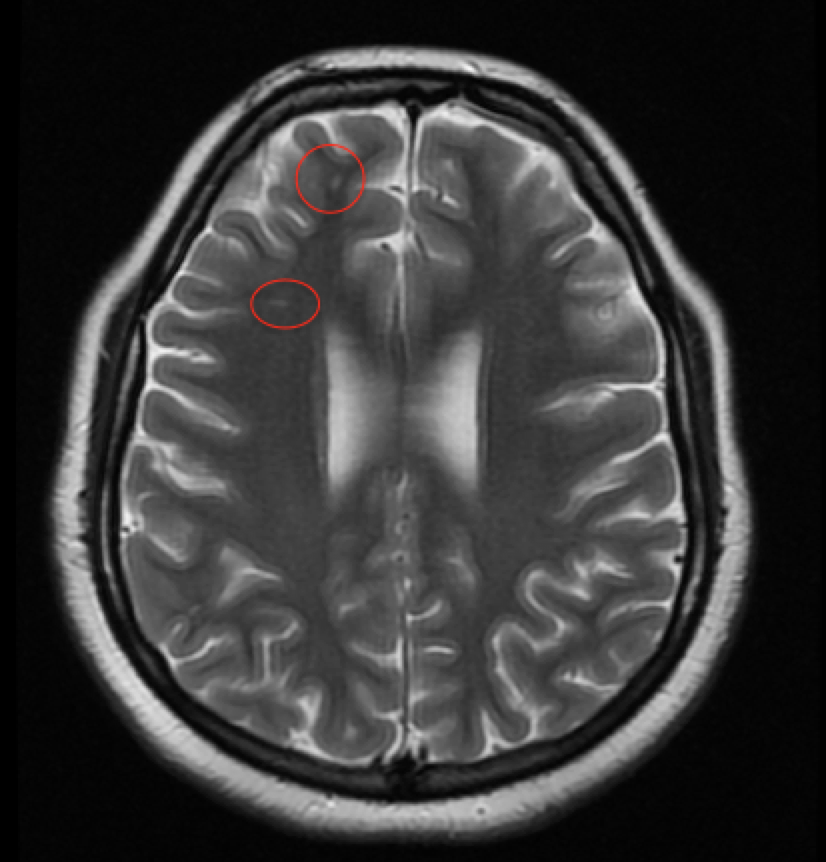

Diagnostic tests. Computed tomography (CT) and CT angiography (CTA) performed in the emergency department showed no signs of hemorrhage or vascular occlusion. Later, magnetic resonance imaging showed punctate foci of T2/FLAIR (fluid-attenuated inversion recovery) hyperintense signal in the periventricular and deep white matter of the frontal lobes, which may be sequelae of migraines (Figure 2).

Figure 2. T2-weighted MRI of the brain taken on the day of presentation. Circled in red are two examples of the punctate hyperintense signal seen in the periventricular and deep white matter of the frontal lobes. These changes likely are sequelae of migraines.